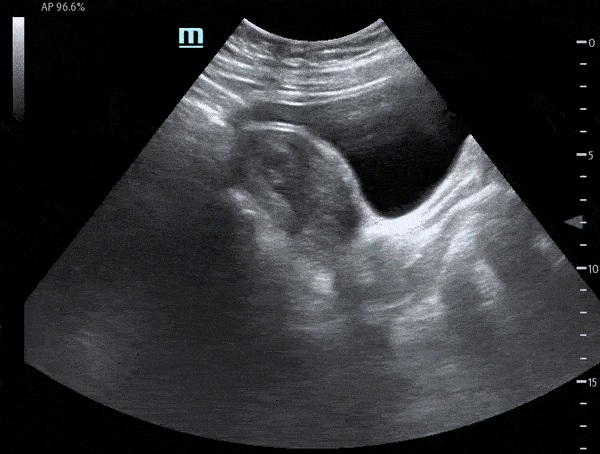

OB/Gyn - Fetal Pole with Cardiac Motion - Sagittal

Sagittal view of uterus demonstrating fetal pole. A subtle flicker within the fetal pole can be seen consistent with cardiac motion. Michael Macias